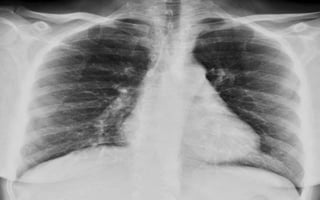

CASOS PATOLOGICOS

1. Marcado aumento del

índice cardiotorácico.

2. La punta del corazón

se dirige al diafragma

por dilatación

biventricular.

3. Aumento del tamaño

de la aurícula derecha.

1. Aumento del índice

cardiotorácico.

2. APEX se dirige hacia abajo del

diafragma por dilatación delVI.

3. Aumento de la densidad

pulmonar bilateral con

distribución perihiliar y basal,

aspecto algodonoso,

confluente, límites mal

definidos borrosidad vascular

(InfiltradoAlveolar).

Cardiomegalia. Hipertensión arterial pulmonar